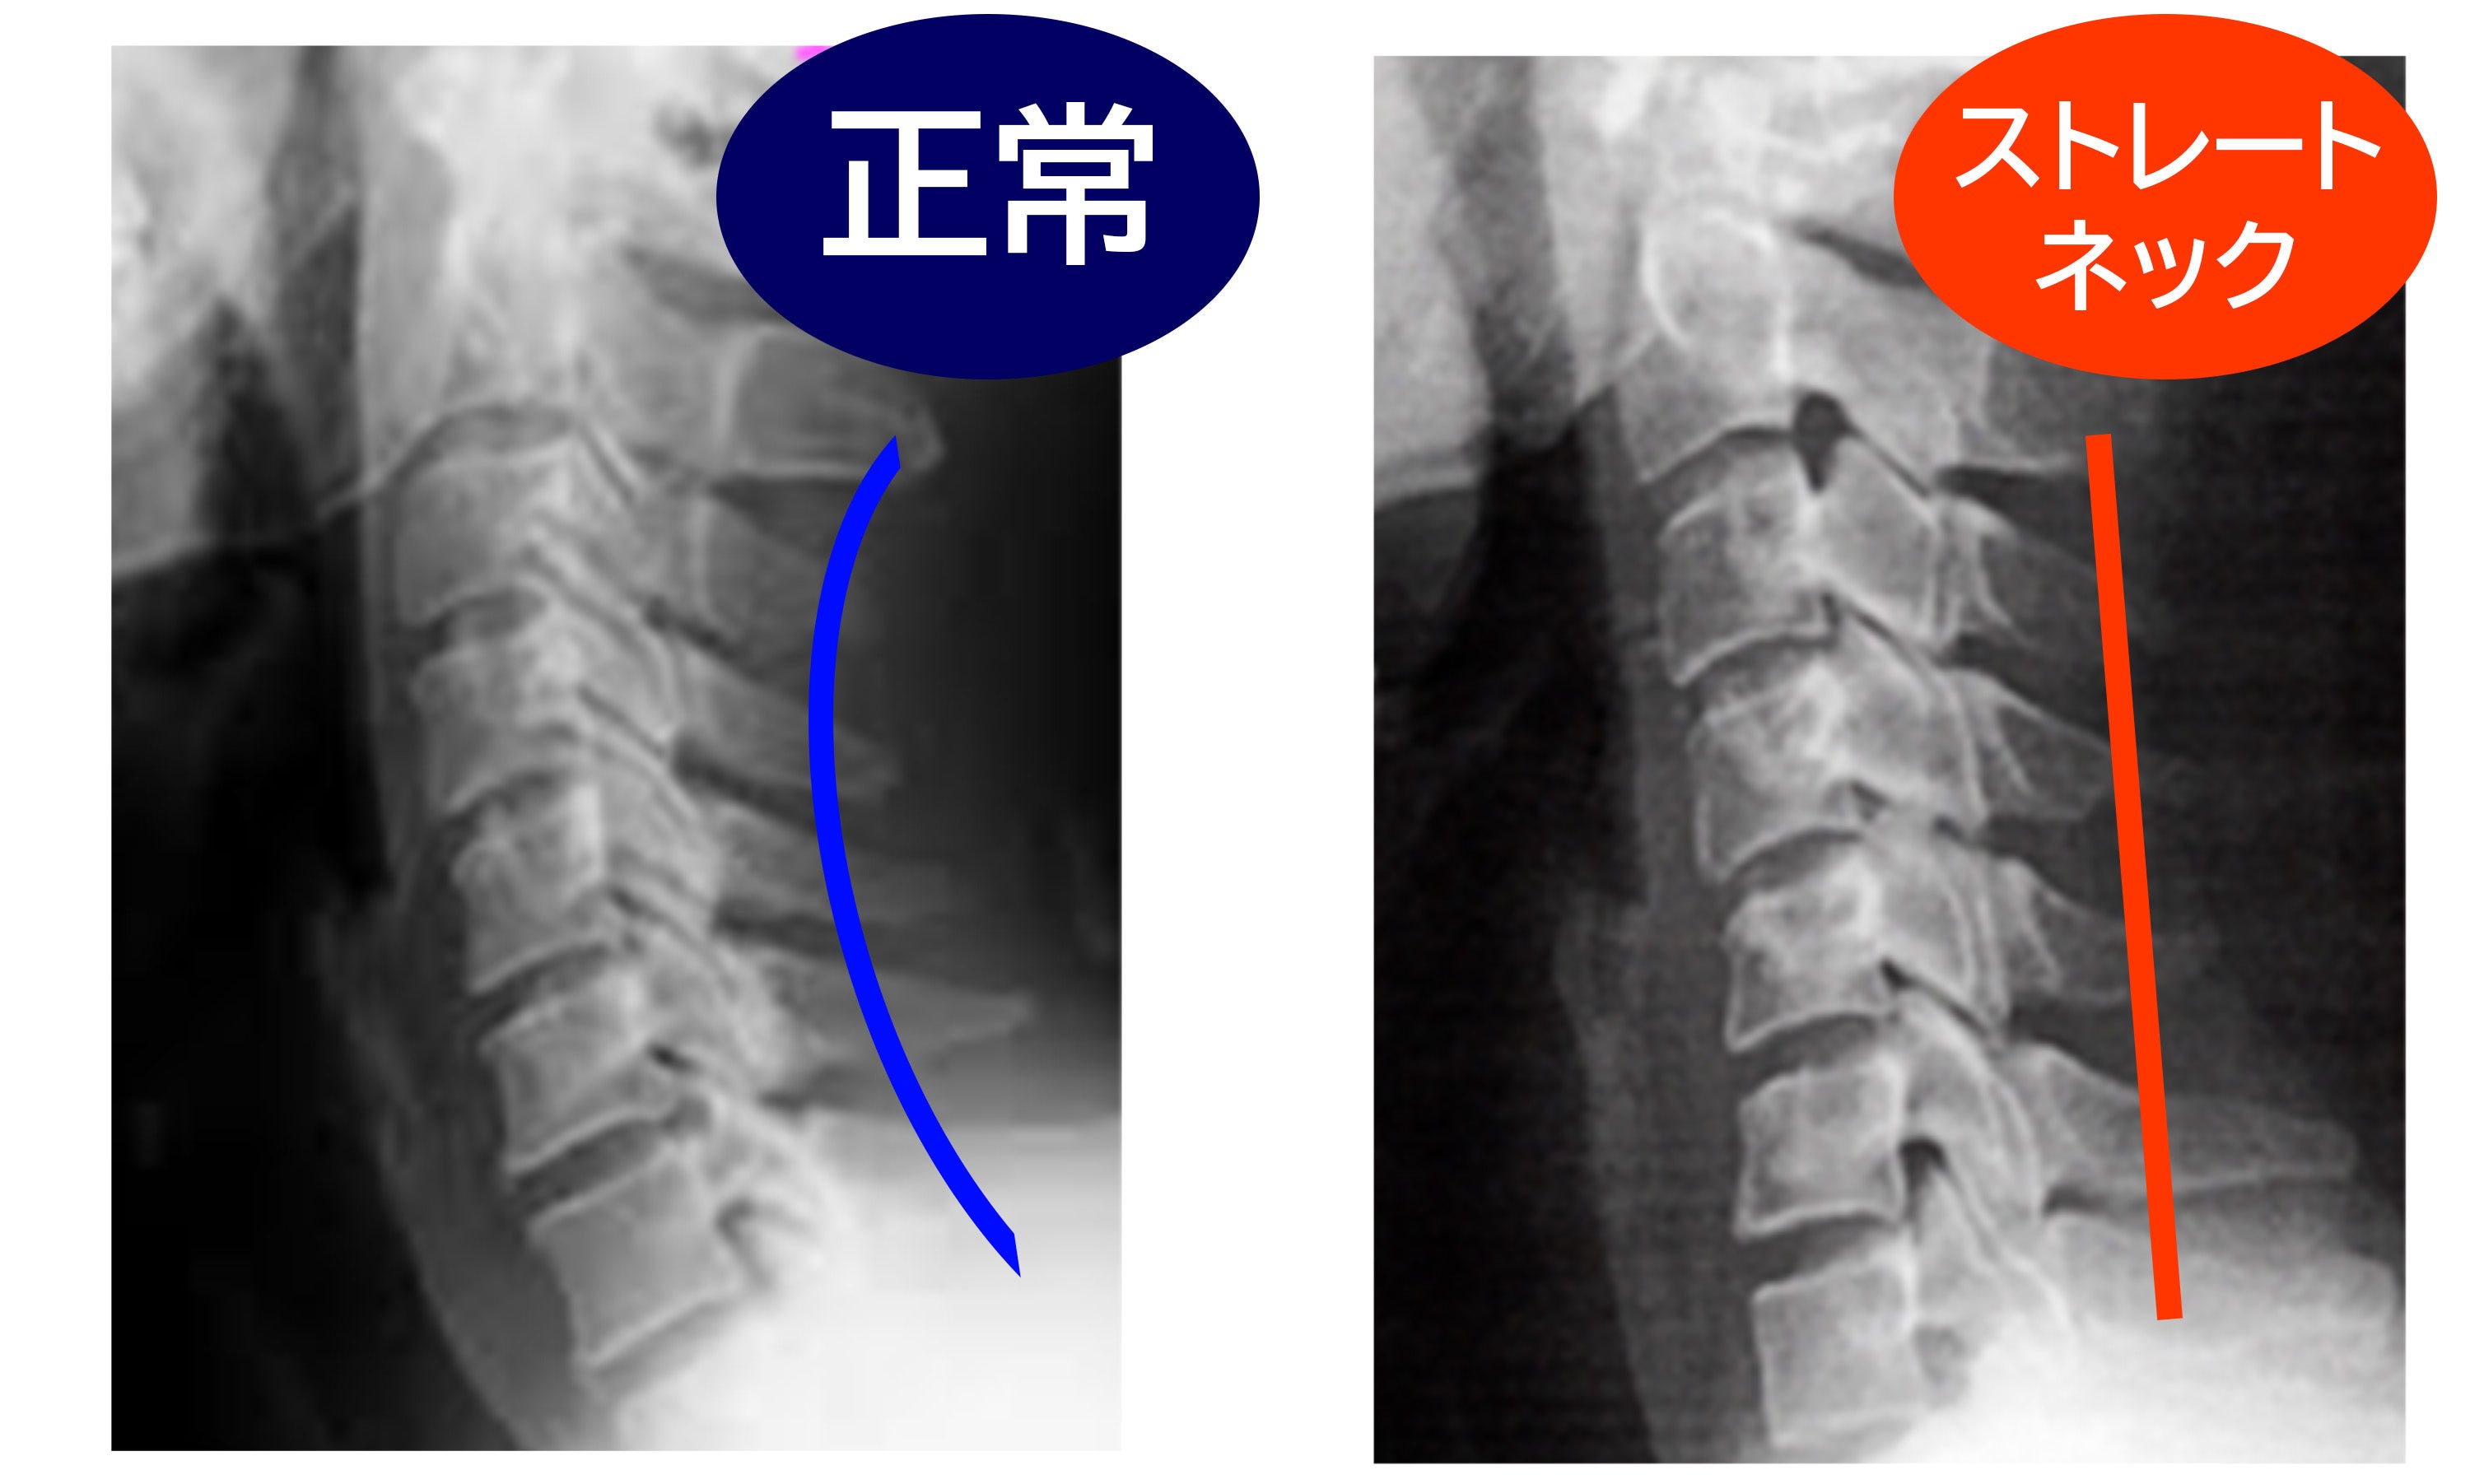

現代に蔓延するストレートネックを何とかしたい。

A: 頸椎太郎は、床に置いてその上に仰向けになり、首をサポートするように位置を調整して使用します。毎日8分間使用することで、首や肩の筋肉をストレッチし、リラックスさせることができます。ストレートネックの改善や、正常な頚椎のカーブを取り戻すことを目指しています。